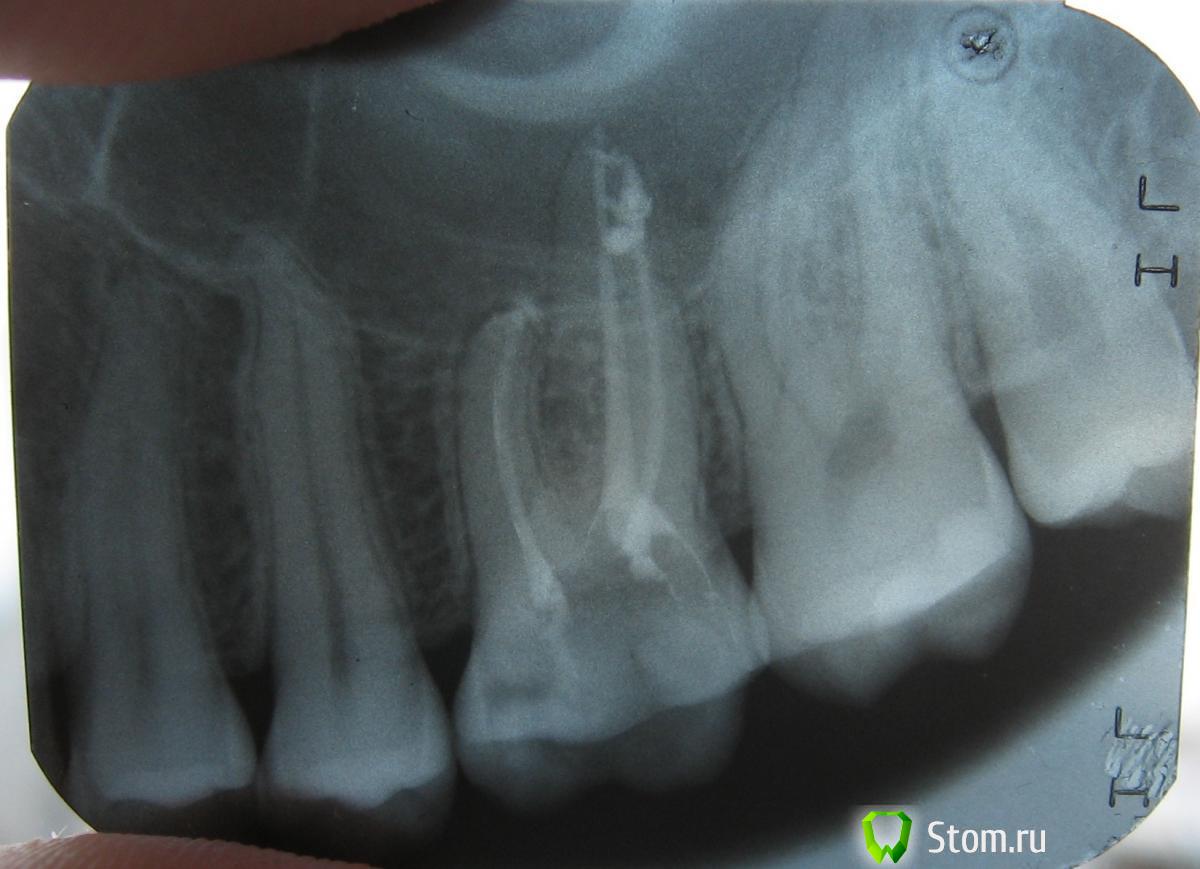

Awaking Опубликовано 28 ноября, 2011 Поделиться Опубликовано 28 ноября, 2011 (изменено) Сначала 6ой зуб сверху лечили от кариеса, но затем сразу после лечения он продолжал реагировать на холодное и давление. Прошел месяц, а реакция на холодное (немного на горячее) и постукивание осталась. 4 дня назад на месте, где начинается щека над зубом стало немного больно при надавливании. Ощущение, будто раздражение. Покраснения и опухания нет. После полоскания травами стало спадать. Возможно это раздражение пошло из-за зубной нити, которой накануне до крови поранил десну в этом месте.Сегодня пришел на прием. Стоматолог решил удалить нерв, в результате чего пломбировочный материал вышел за пределы канала зуба. На снимке виден выход на 4мм. Сейчас стоит временная пломба. Фото рентгена прилагаю.Насколько все плохо и какие могут быть последствия? Я так понимаю, этот пломбировочный материал уже не вытащить оттуда? P.S. Во время заделывания канала врач разогрел инструмент зажигалкой и что-то прижег в зубе. Зачем это 0.о Изменено 28 ноября, 2011 пользователем Awaking Ссылка на комментарий

Stomart Опубликовано 28 ноября, 2011 Поделиться Опубликовано 28 ноября, 2011 Насколько все плохо и какие могут быть последствия? Я так понимаю, этот пломбировочный материал уже не вытащить оттуда? P.S. Во время заделывания канала врач разогрел инструмент зажигалкой и что-то прижег в зубе. Зачем это 0.о Необходимо понаблюдать за зубом несколько дней, может и ничего не быть. Врач обрезал шрифты, которыми пломбировал каналы, горячим инструментом. Ссылка на комментарий

Stomart Опубликовано 28 ноября, 2011 Поделиться Опубликовано 28 ноября, 2011 Извиняюсь за Т9 ) Врач обрезал "штифты". Ссылка на комментарий